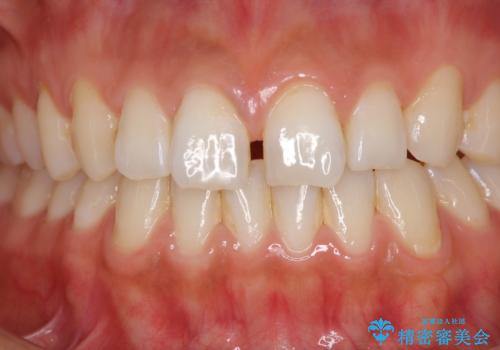

前歯の隙間をオールセラミックで閉じる

- 上の前歯の隙間を気にして来院された患者様です。

矯正治療により前歯を閉じるという治療を第一選択肢として提案しましたが、期間と費用からオールセラミッククラウンによる補綴治療を行うこととしました。

虫歯もない前歯を削ることは、処置をする者として心苦しいのですが、患者様は矯正治療は選択しないとのことだったので、オールセラミッククラウンにて補綴治療を行いました。

短期間で思い通りの仕上がりとなり、患者様には大変満足していただきました。